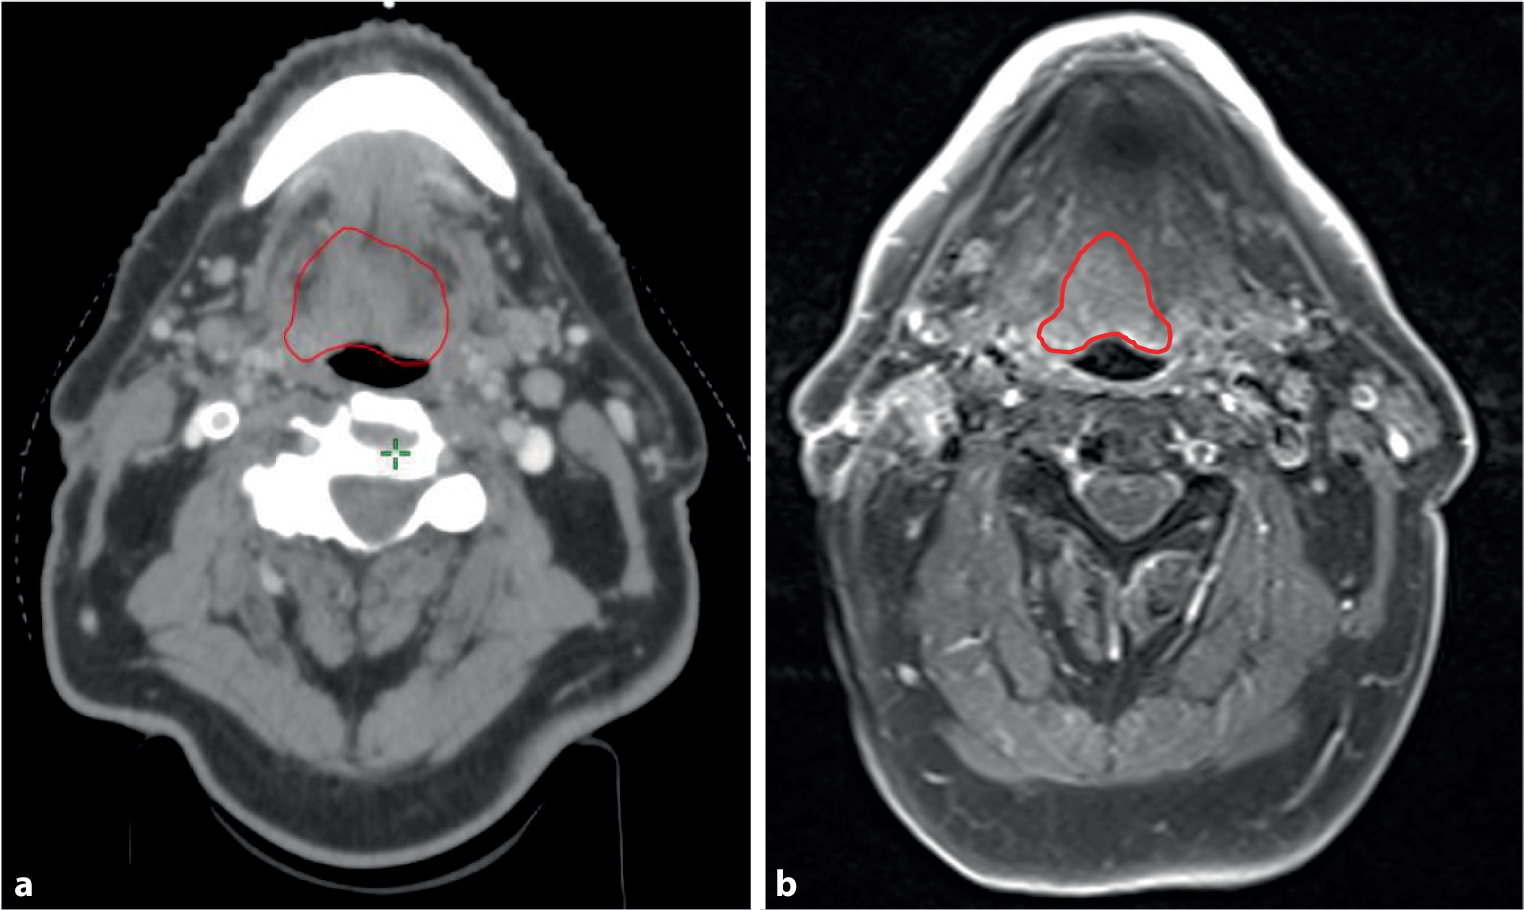

With technological improvements in RT delivery leading to better dose conformity, such as IMRT, volumetric arc radiotherapy (VMAT) and proton therapy, additional attention may be dedicated to reducing the overall RT dose to healthy tissue without compromising the tumour dose. A reduction in the dose to critical structures, e.g. the salivary glands, resulted in reduced long-term toxicity and improved quality of life [12]. Together with improved target definition using advanced imaging (magnetic resonance imaging [MRI], PET/CT), improved accuracy of radiation delivery using image-guided radiotherapy (IGRT) and even reacting to tumour volume changes during the treatment course through image-guided adaptive radiotherapy (IGART), the overall toxicity can be reduced without treatment de-intensification to the tumour site ([13], Figs. 2 and 3).

Fig. 2

Tumour volume (red) definition using computed tomography (CT) and MRI. MRI allows better soft tissue contrast for head and neck cancers with improving the precision of contouring. This can result in smaller volumes with reduction of irradiated volume: a CT-based target contouring, b MRI-based target contouring

Before treatment, the risk–benefit profile should be careful evaluated for every patient, using parameters like patient performance status, age and comorbidities. Initial staging using clinical information and multimodality imaging (CT, PET/CT and MRI) should be performed in every patient (Fig. 2). HPV-positive oropharyngeal cancer represents a unique subgroup of HNSCC; a careful approach and further randomized trials are required to assess safety and efficacy of de-intensification treatment.